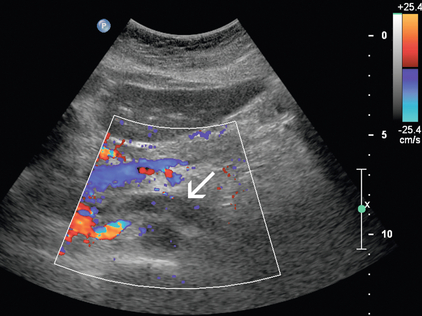

Диагноз РВТ основывается на обнаружении тромба, заполняющего почечную вену ( рис. 9-21 ), или неокклюзионного тромба, окруженного венозным потоком. В некоторых случаях вена может быть расширена тромбом. Отсутствие кровотока в почечной вене без признаков тромба может указывать на RVT; однако демонстрация низкого уровня цветового сигнала внутри вены при допплерографии не исключает возможности неокклюзионного или окклюзионного тромба почечной вены. Монофазные венозные волны являются аномальными, но не специфичными для RVT. Из-за возможности распространения тромба краниально в пределах НПВ ( рис. 9-22 ) и влияния на клиническое лечение, НПВ следует визуализировать в рамках сонографического исследования при оценке РВТ.

РИСУНОК 9-21. Тромб почечной вены. При цветной допплерографии эхо-сигналы низкого уровня заполняют левую почечную вену при отсутствии полного допплеровского заполнения ее просвета (стрелка).